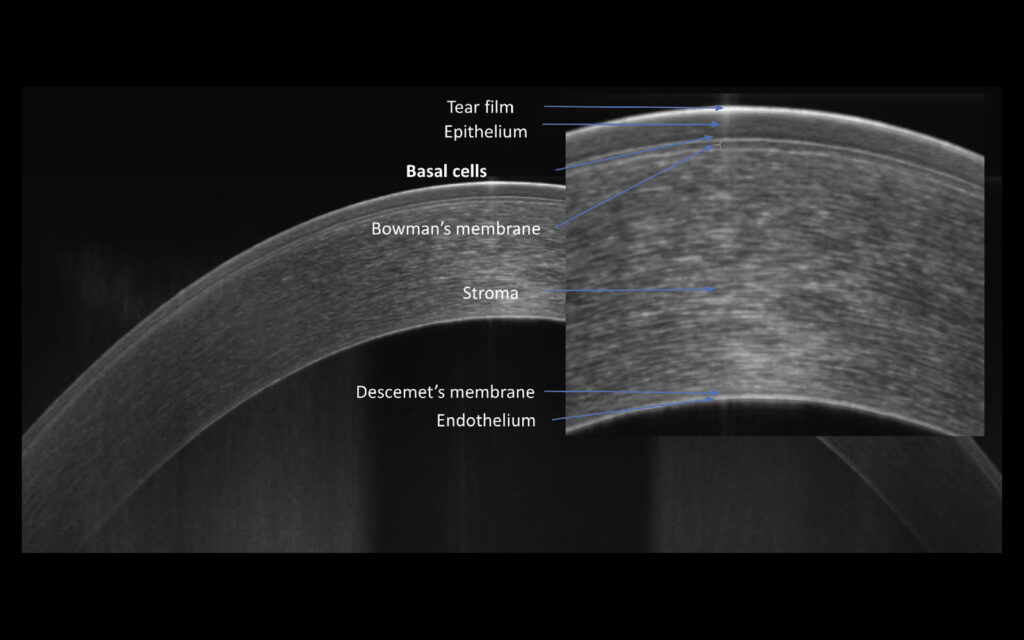

Cornea and Epithelium

AI-supported analysis of the anterior segment enables detailed evaluation of corneal structures, including epithelium and pachymetry. Presentation of results for both eyes supports quick and precise assessment, while epithelial and pachymetry maps are included as part of the standard package.

Cornea and Epithelium icon

AI-supported analysis of the anterior segment enables detailed evaluation of corneal structures, including epithelium and pachymetry.

Presentation of results for both eyes supports quick and precise assessment, while epithelial and pachymetry maps are included as part of the standard package.

OCT Topography icon

New OCT Topography *

OCT Topography provides detailed corneal mapping based on high-resolution OCT data, enabling precise evaluation of corneal thickness distribution and structural profile.

The updated Topography algorithm (T2) enhances corneal surface reconstruction through improved modeling, increasing resistance to noise and improving the reliability of computed parameters. A higher number of B-scans supports more accurate data acquisition and analysis.